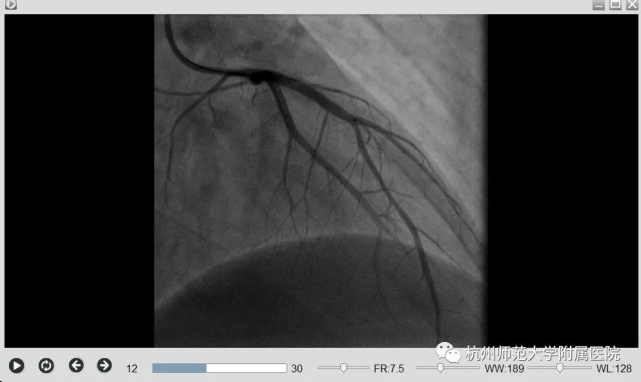

刘主任立刻启动胸痛中心绿色通道,通知患者家属后,刘主任带领胸痛团队立即将患者送至导管室,经过冠脉造影证实,患者前降支血管(为心脏收缩的主要功能血管)完全闭塞,符合De-Winter综合征的表现,立即予以开通闭塞的血管,植入支架1枚,小方心脏血管血流恢复,胸痛症状明显缓解,血压心率逐渐平稳下来。

手术前后对比图